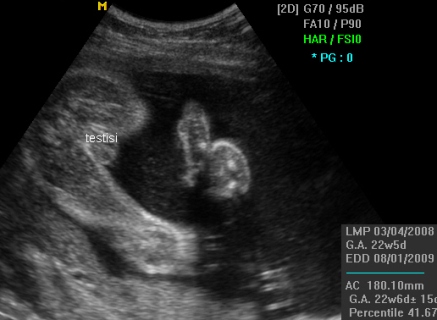

Потврда на машко бебе

Еве уште едно момченце